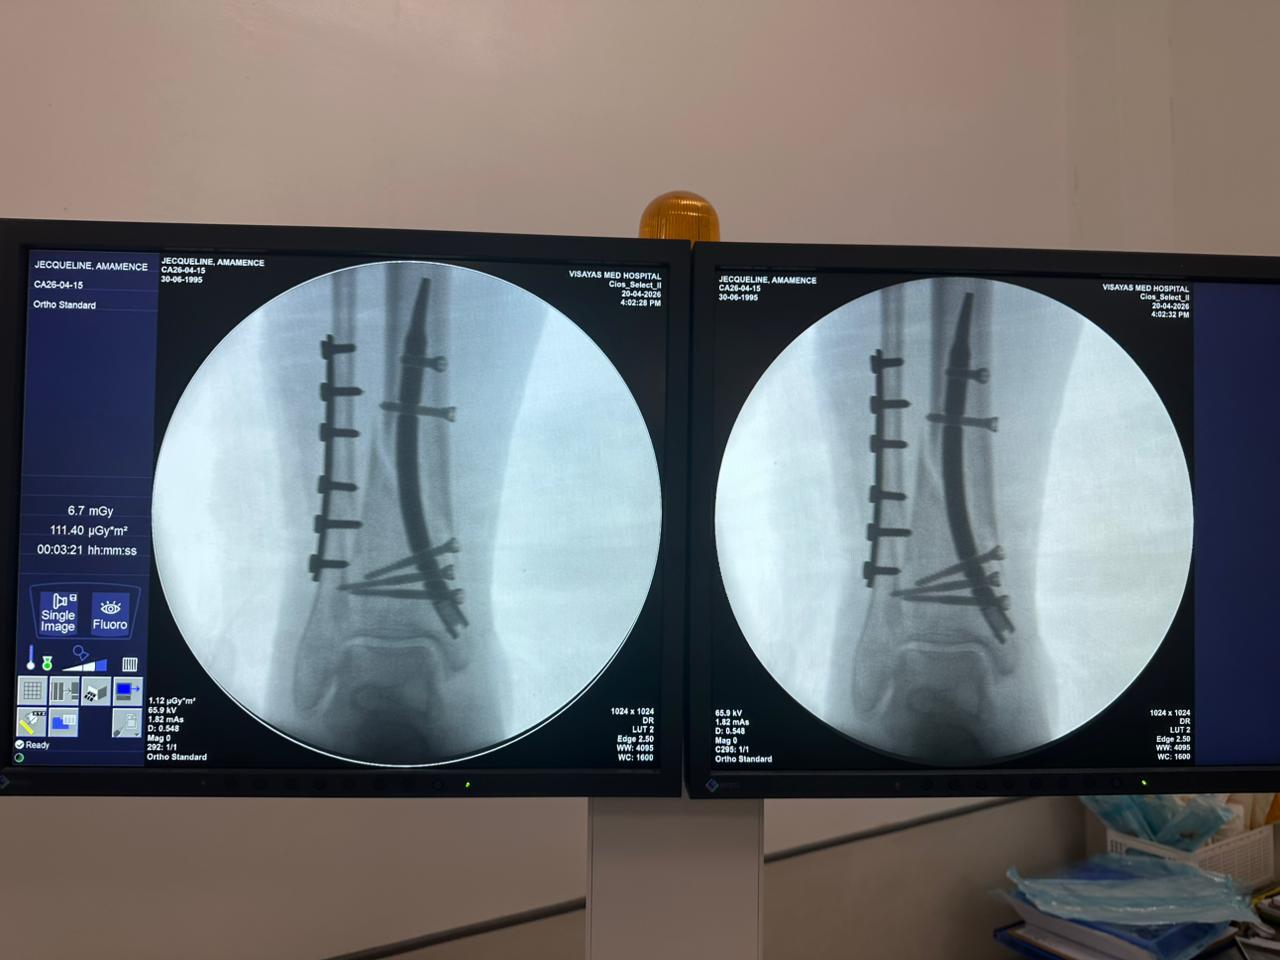

Distal Tibial Nail Fixation Case Study with Fibular Plate Support

Imaging:

Intraoperative C-arm fluoroscopy, AP and lateral views

Case Summary:

This case involved distal tibial fixation using an intramedullary distal tibial nail. Intraoperative fluoroscopy confirmed the position of the nail, distal locking screws, and fibular plate fixatio